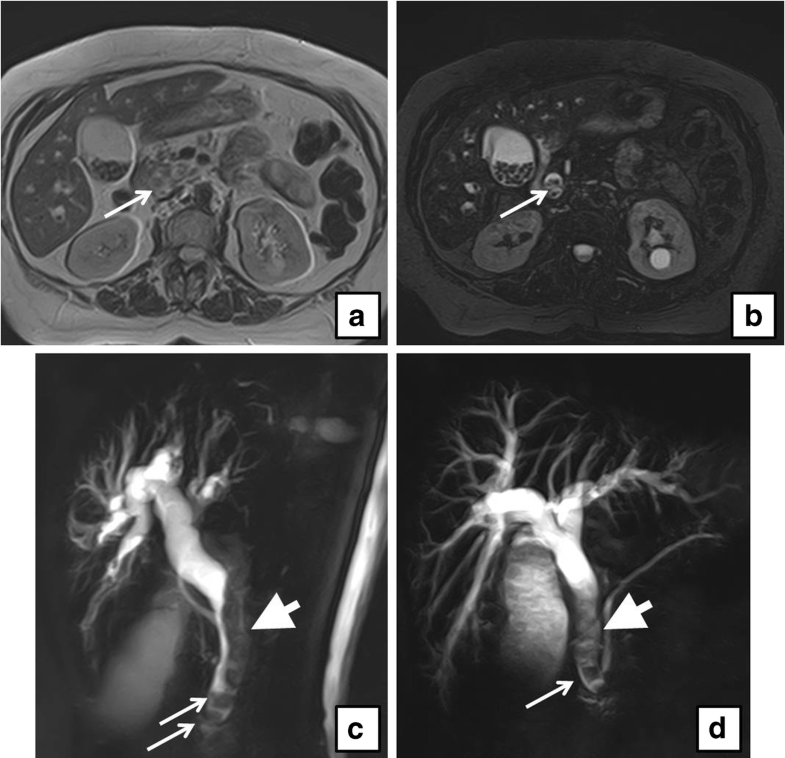

From www.researchgate.net

MRI/MRCP examination of the abdomen with and without contrast. (a, b What Is A Mri With Mrcp Mrcp is a type of. Mrcp stands for magnetic resonance cholangiopancreatography. Magnetic resonance cholangiopancreatography (mrcp) is a special type of mri that uses computer software to image the pancreatic and bile ducts, areas where tumors. Mri stands for magnetic resonance imaging. It uses strong magnetic fields and radio waves to produce an image of your internal organs. Magnetic resonance cholangiopancreatography. What Is A Mri With Mrcp.

CT, MRI, and MRCP scans. (A) Contrastenhanced CT and (B, C What Is A Mri With Mrcp Magnetic resonance cholangiopancreatography (mrcp) is a special type of mri that uses computer software to image the pancreatic and bile ducts, areas where tumors. Mrcp is a type of. Mrcp is a type of magnetic resonance imaging (mri) scan. A magnetic resonance cholangiopancreatography (mrcp) scan is a medical scanning method that uses radio waves and a magnetic field to. Mrcp. What Is A Mri With Mrcp.

MRCP with contrastenhanced MRI and diffusionweighted MRI shows What Is A Mri With Mrcp What is mrcp scan used for? It uses magnetic resonance imaging to visualize the biliary and pancreatic. Mri stands for magnetic resonance imaging. Magnetic resonance cholangiopancreatography (mrcp) is a special type of mri that uses computer software to image the pancreatic and bile ducts, areas where tumors. Mrcp stands for magnetic resonance cholangiopancreatography. It uses strong magnetic fields and radio. What Is A Mri With Mrcp.

(MRCP) Cuts showing the pancreatic mass (white arrows) as it appeared What Is A Mri With Mrcp Mrcp is a type of. What is mrcp scan used for? Mri stands for magnetic resonance imaging. A magnetic resonance cholangiopancreatography (mrcp) scan is a medical scanning method that uses radio waves and a magnetic field to. Mrcp stands for magnetic resonance cholangiopancreatography. An mrcp scan is a type of mri scan that you have in an mri scanner. It. What Is A Mri With Mrcp.

a MRIMRCP imaging of an 83yearold male with a 2.7cm intraductal What Is A Mri With Mrcp A magnetic resonance cholangiopancreatography (mrcp) scan is a medical scanning method that uses radio waves and a magnetic field to. Mrcp stands for magnetic resonance cholangiopancreatography. Mri stands for magnetic resonance imaging. Magnetic resonance cholangiopancreatography (mrcp) is a special type of mri that uses computer software to image the pancreatic and bile ducts, areas where tumors. An mrcp scan is. What Is A Mri With Mrcp.